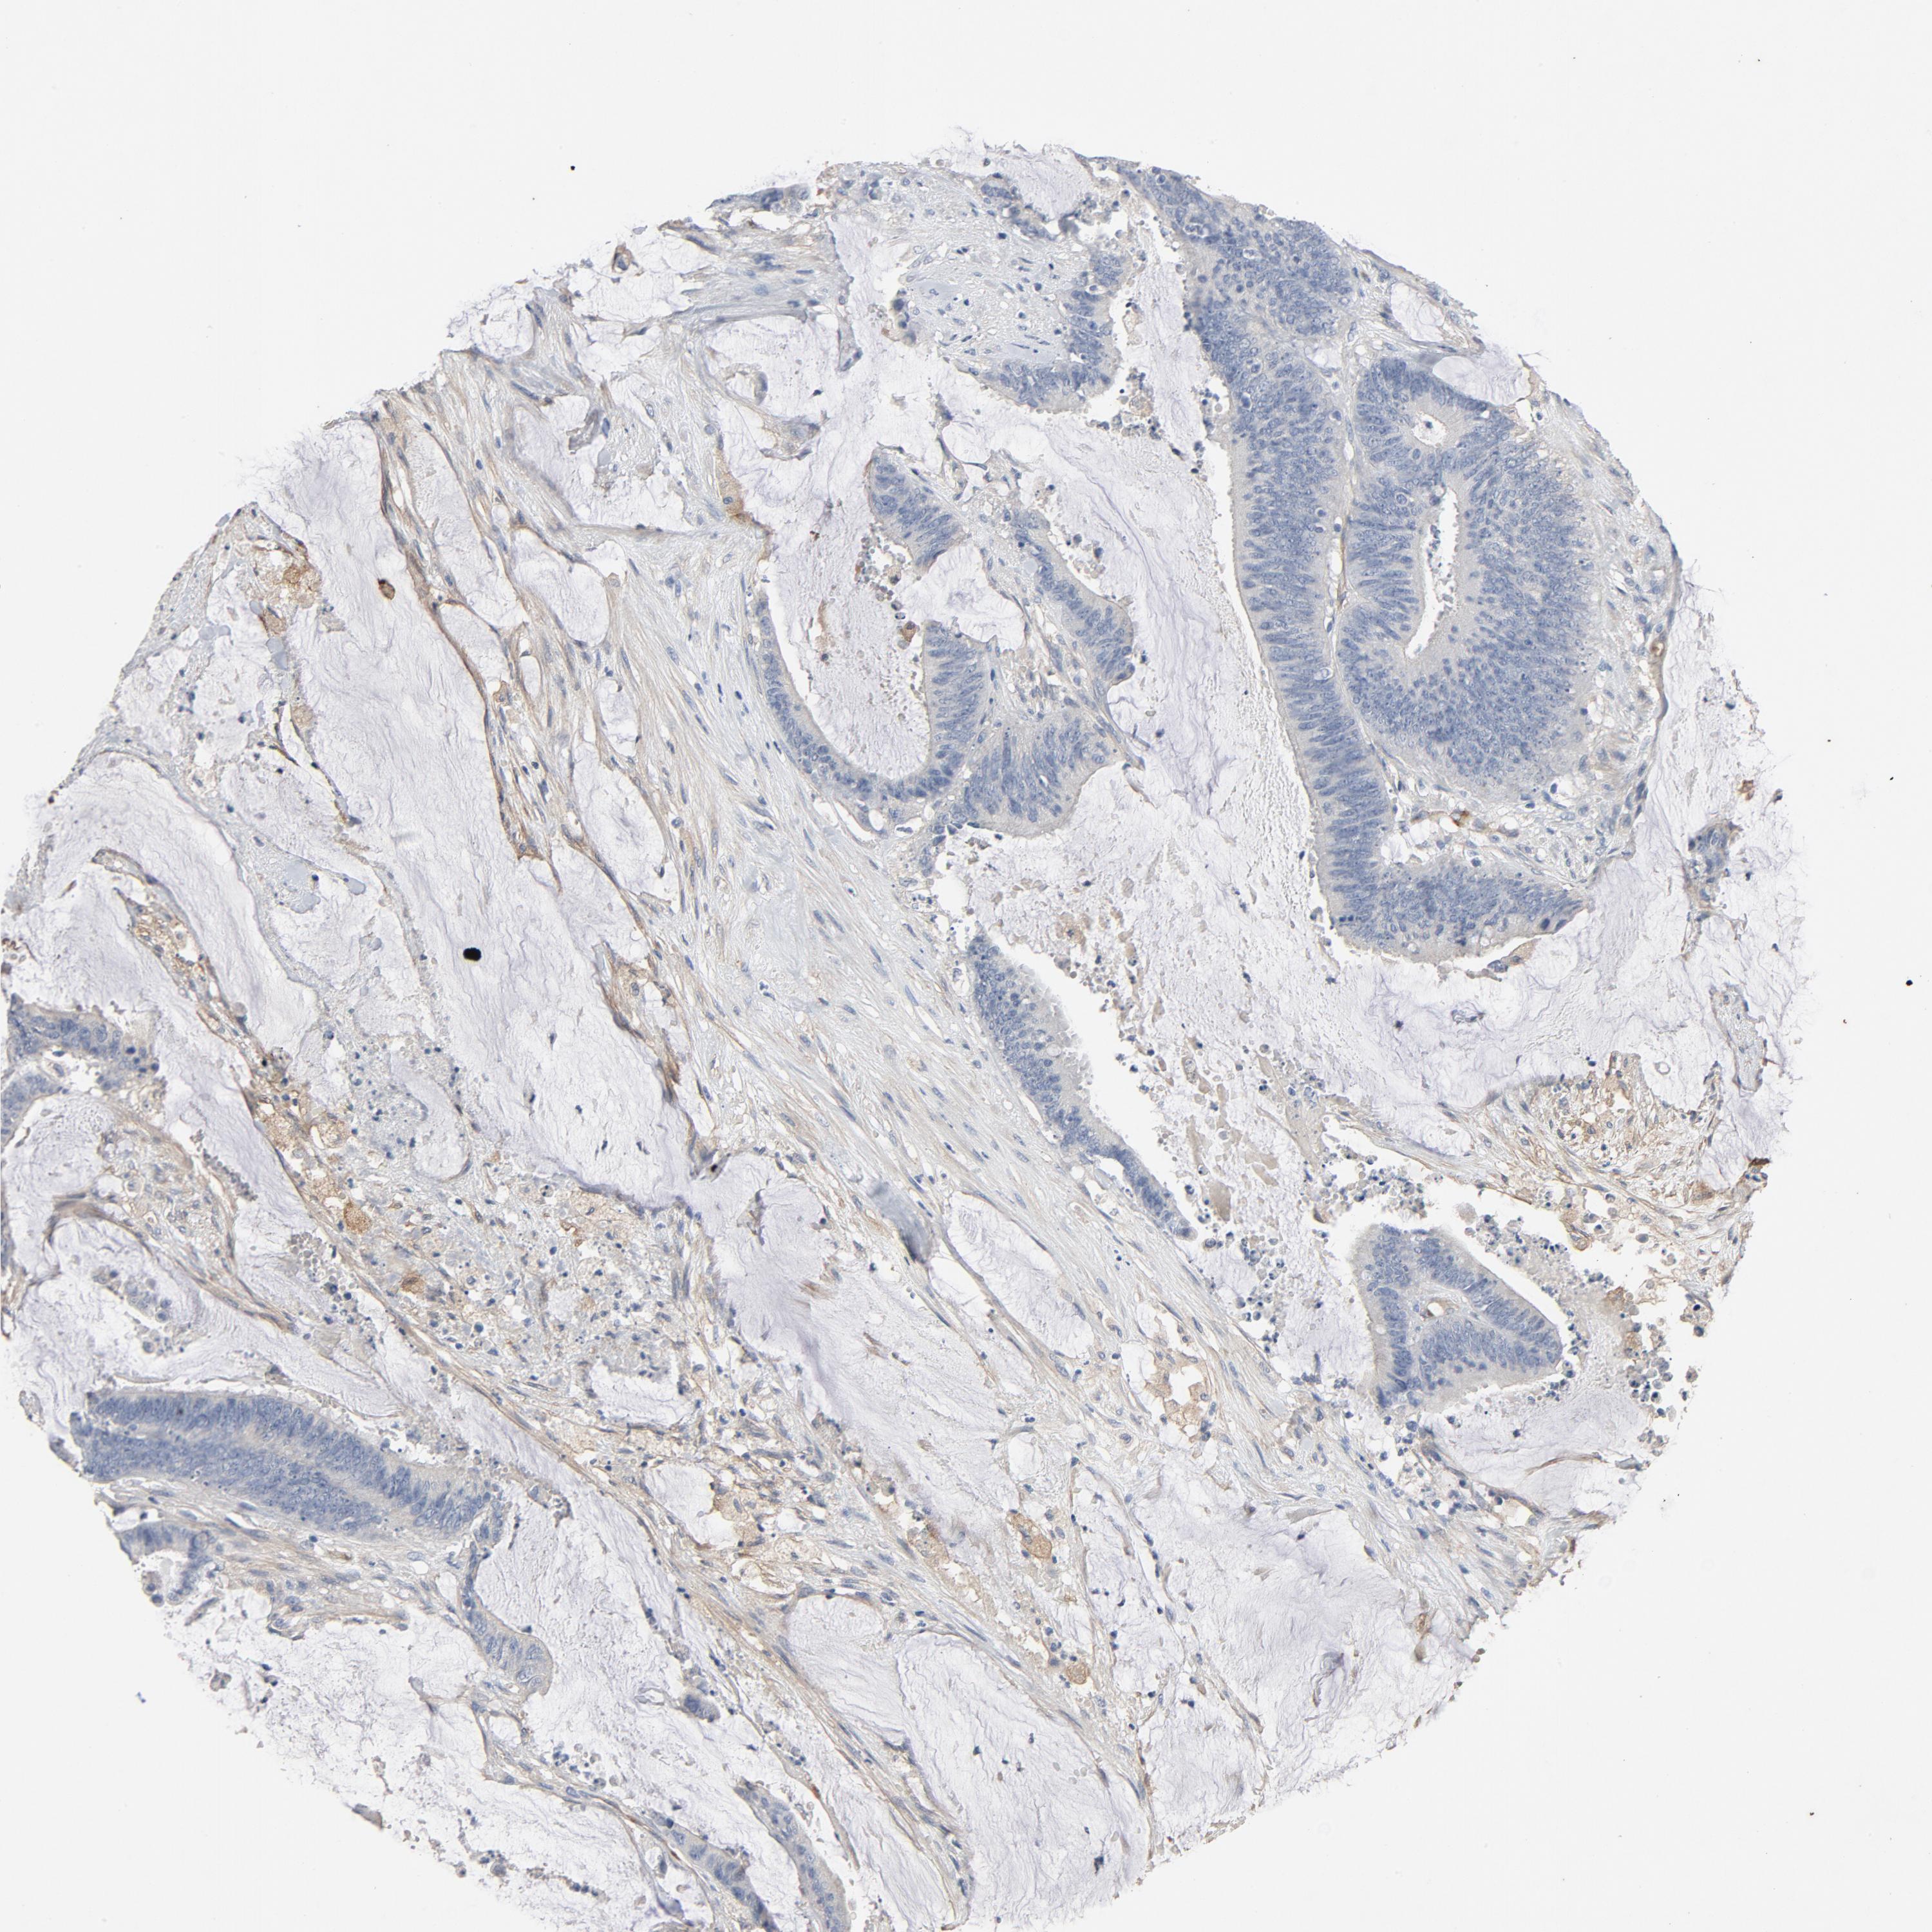

CANCER COLORECTAL CANCER Show tissue menu

Colorectal cancer

Human cancer

Colon adenocarcinoma